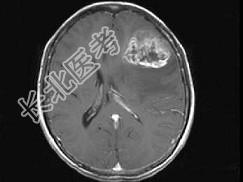

- 单项选择题女,52岁, 头痛伴呕吐2周,根据所提供图像, 最可能的诊断是 ( )

A、转移瘤

B、星形细胞瘤Ⅱ级

C、星形细胞瘤Ⅰ级

D、少枝胶质细胞瘤

E、脑脓肿